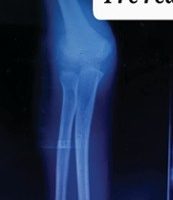

Informed consent was obtained from all participants. Demographic details and relevant medical history were collected using a structured proforma. Clinical examination and surgical intervention were carried out using standard procedures at the SBMCH. [Fig. 1] [Fig. 2] [Fig. 3] Postoperative evaluation for implant loosening was done through serial radiographs, specifically assessing for radiolucency at the bone-cement interface. Functional outcomes were assessed 26 using the CONSTANT-Murley score and UCLA shoulder score. All data were entered in Microsoft Word and analyzed using SPSS software version 24. [Fig. 4].

Figure 4: Post-operative X-ray.